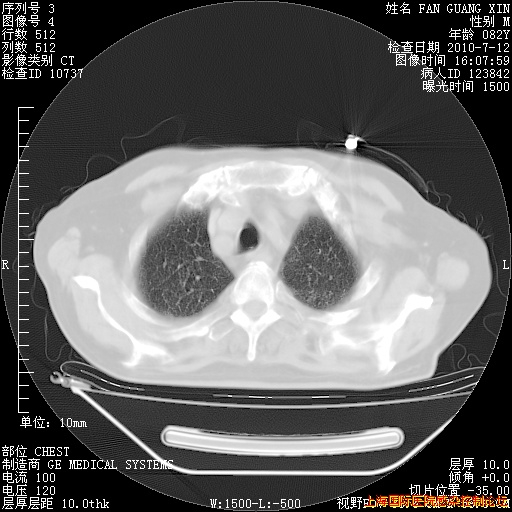

补发6月12日肺部CT肺窗

6月12日肺窗

6月12日纵膈窗

今天复查CT

今天CT

整整相隔30天的肺部CT好像有所好转啊。甲强龙减量第3天,需要观察体温。

海管,自昨日你和我通完话后,不知您岳父消化道症状有无缓解?体温怎样?阅读7.12日胸部ct,个人认为目前激素治疗是有效的,甲强龙减量是适宜的。因在抗痨治疗,需密切观察肝功、肾功能和血常规。不过,老年、长期住院和大量使用激素,很担心菌群失调发生